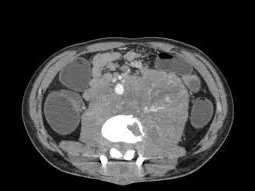

- To understand and review imaging features of lymphoma

- To review lymphoma staging on appropriate imaging techniques including CT and PET-CT